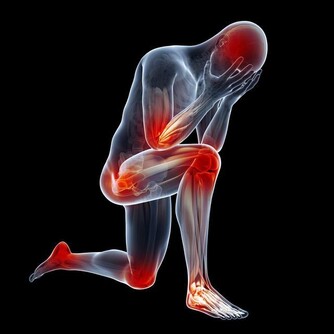

夏天雨水多,且多陣雨、暴雨,如果不能很好的防護躲避,硬冒雨涉水前行並滯留時間過長,很容易使得寒濕之氣進入人體,損傷陽氣,而患發熱、腹瀉、嘔吐等疾患,同時也為風濕性關節炎、類風濕性關節炎等疾病埋下病根。